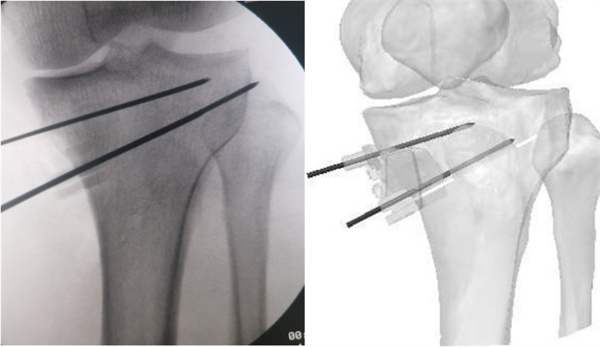

术中X线与AI术前设计对比照片

术前经过心内科、神经内科、皮肤科、临床营养科及麻醉科的多学科团队联合评估,手术于2月28日如期开展。术中,李兵借助AI+3D打印导板,精确放置导板于截骨区,快速准确定位合页位置、截骨位置、方向和深度,实现精准截骨。同时,楔形块精准撑开,保证撑开角度不丢失,实现手术目标精准落地。

李兵表示,手术的顺利开展得益于3D打印PSI导板的应用,术中极大地简化了手术操作步骤,避免了传统手术中反复调整力线和透视确认的繁琐流程,减少了术中透视次数,降低了医护人员及患者的辐射伤害,有效缩短了手术时间。